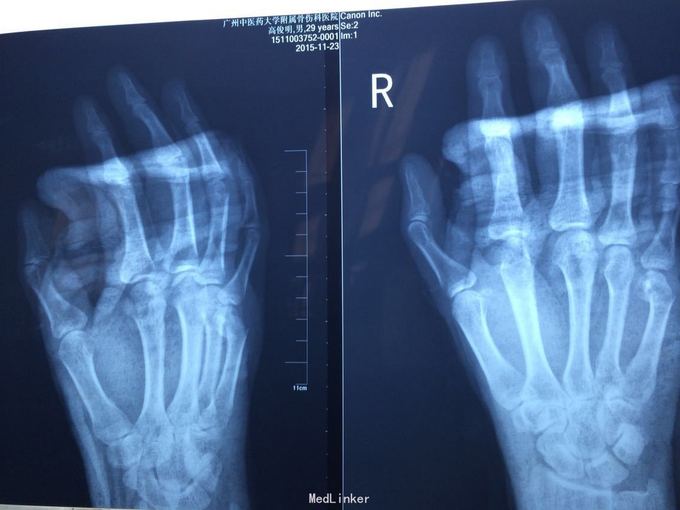

黄某某,男,29岁。 主诉:右掌第五节疼痛肿胀伴有活动受限2周余。 病史:患者16日前右手一拳打到墙上,致使右掌第五节疼痛,肿胀,活动受限,随即到骨伤科医院诊治,主诊医生拍X片后建议患者行手术治疗,但患者可虑到自己年轻,加上咨询了一些做医生的亲朋好友的意见,决定保守治疗。患者自诉当主诊医生听到患者不愿意做手术后,就建议行石膏固定治疗,当时就一个医生给患者进行手法复位,基本没有效果,但主诊医生照样行石膏固定。2周后遂来我院治疗,现患者右掌第五节疼痛,肿胀,活动受限,无其他不适。

查体检查:右掌第五节压痛明显,可扪及骨擦音,纵向叩击痛。

诊断:右掌第五节掌骨骨折(气滞血瘀) 处理:手法复位后行小夹板固定,口服接骨七厘片,5#/次,bid,隔两天换药。

1、骨伤科医院的主诊医生为什么在复位效果不佳的情况下还行石膏固定? 2、因为患者2周后才来本院复诊,重新手法复位的可能性比较小,所以效果不佳,可患者坚决不行手术治疗,接受小夹板固定。请问各位同行日后掌骨畸形愈合后,功能影响大吗?